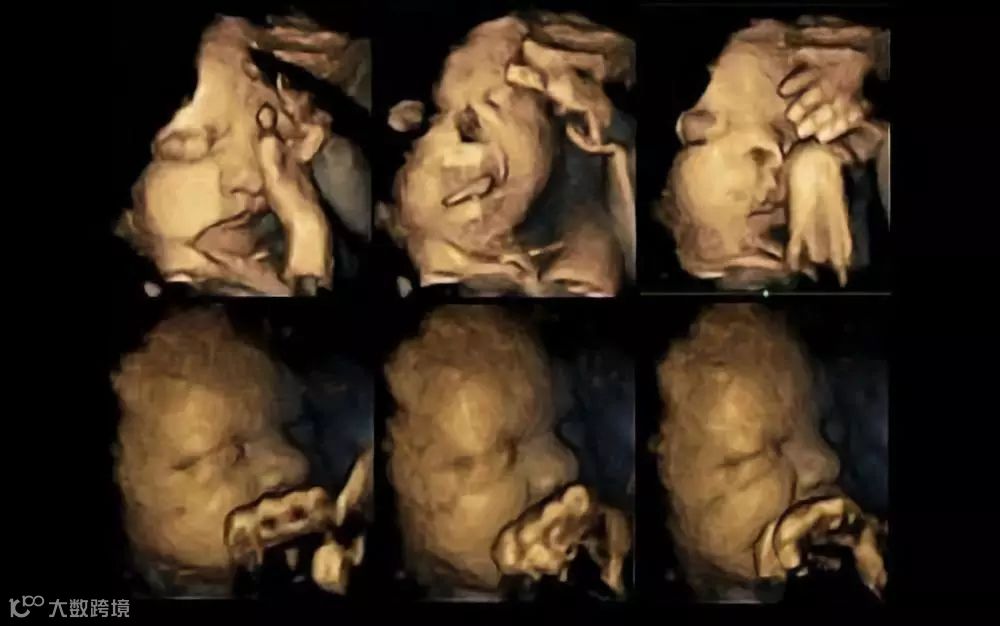

英国的一项研究揭示,怀孕妇女吸烟有害胎儿健康,可能反映在胎儿的面部表情上。